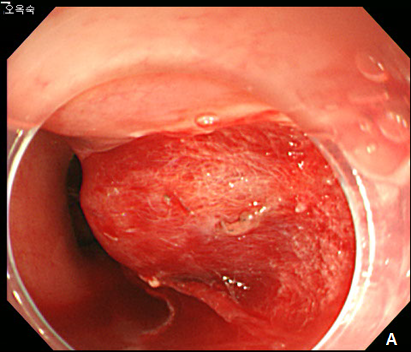

A 42-year -old woman was refferred to our hospital for further evaluation of dysphagia. The patient had no specific past history, and physical examination showed no remarkable findings. Laboratory examination also showed all negative findings. An esophagogastroduodenoscopy (EGD) was performed, and revealed a large, 4 cm sized, elongated SET at upper to mid esophagus, 23~27 cm from incisor (Figure 1A). An endoscopic ultrasonography (EUS) was performed to further evaluate the nature and origin of esophageal SET, which showed a homogenous hypoeshoic mass originated from muscularis propria layer (Figure 1B). We decided to perform endoscopic resection of esophaegeal SET for relief of symptom, and conventional ESD technique was used.2 Briefly, lesion boundaries were identified and marked using argon plasma coagulation connected to an electrosurgical generator (Erbe ICC 200W; Erbe Elektromedizin GmbH, Tübingen, Germany). After injection of a 0.9% saline solution mixed with epinephrine (dilution rate 1:10,000) and indigo carmine dye into the submucosal layer, an initial incision was made 3~5 mm from the regular mucosal layer in a regular interval using needle knife (KD-IL-1, Olympus Optical Co. Ltd.). Submucosal dissection was done with insulated-tipped electrosurgical knife (IT knife) (KD-610L, Olympus Optical Co Ltd.). Dissection of the tumor was performed successfully, however, a large mucosal defect was noted after the procedure (Figure 2A-2D). The resected specimen was 4.2 cm in length and 1.5 cm in diameter, and tumor was diagnosed as leiomyoma by histopathologic examination. The patients had no immediate major complications, and discharged 3 days after the procedure. However, 2 weeks later, the patient complained of significant chest discomfort and dysphagia, and a follow-up EGD showed significant stricture at the procedure site where the scope could not be passed. Endoscopic balloon dilatation was performed and repeated 8 times over 4 months, which led to the resolution of the stricture (Figure 3A-3C).

Figure 1 Esophageal subepithelial tumor (SET).

(A) An esophagogstroduodenoscopy (EGD) showed a large (4.0 cm) SET at upper to mid esophagus. (B) An endoscopic ultrasonography showed a large hypoeshoic mass originated from muscularis propria layer.